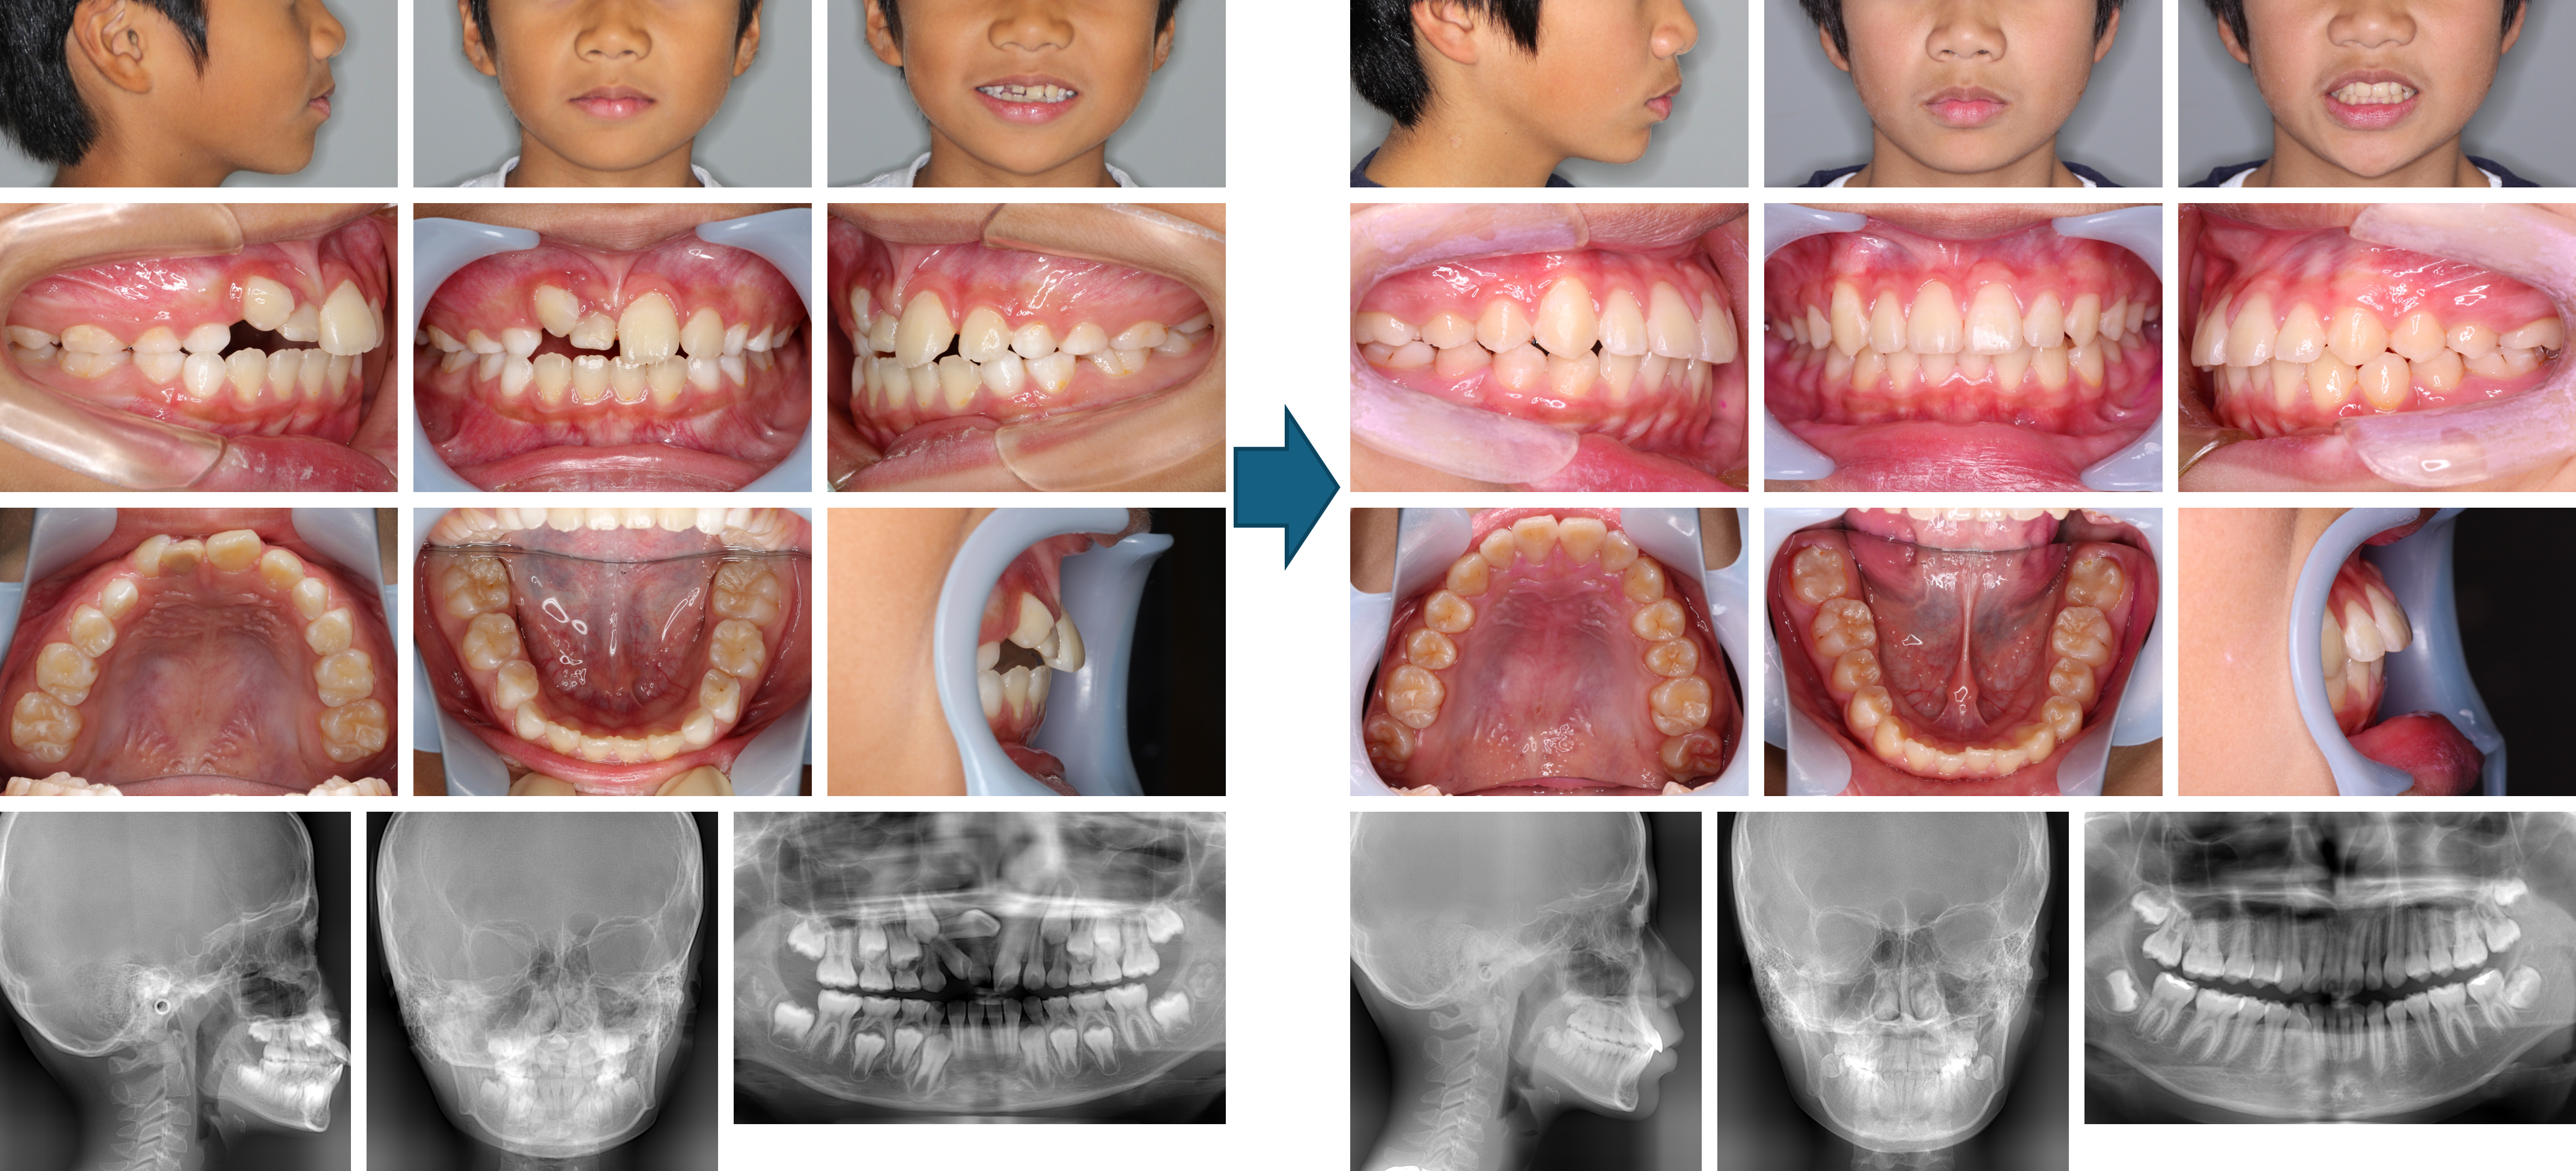

【治療例 K6650】初診時年齢:8歳9か月 / 性別:女性 / 主訴:下の前歯2本が前に出て、全体ガタガタ

治療の概要:下顎骨が大きく前歯部に反対咬合が認められる混合歯列弓症例。チンキャップを使用して下顎骨の成長抑制を行うとともに上顎にはリンガルアーチで前歯部の反対咬合を改善し、その後マルチブラケット装置を装着して緊密な咬合およびきれいな顔貌が得られた症例。

主訴:下の前歯2本が前に出て、全体ガタガタ

診断名:上顎前歯部の反対咬合

使用した主な装置:マルチブラケット装置(審美)、リンガルアーチ、チンキャップ、顎間ゴム

抜歯/非抜歯および抜歯部位:非抜歯

治療期間:4年11か月(第1期治療:9か月、第2期治療:4年2か月)

治療回数:第1期治療:11回、第2期治療:37回

【治療例 K5117】初診時年齢:11歳0か月 / 性別:女性 / 主訴:受け口を治したい

症例の概要:上顎の劣成長および下顎の過成長が認められた骨格性の下顎前突でした。上顎にはクワドヘリックス装置および前方牽引装置を用いて歯列の前方拡大及び前方への成長促進を行いました。その結果、小臼歯を抜歯せず、受け口は改善されました。

主訴:受け口を治したい

診断名:上顎歯列の萌出余地が著しく不足した骨格性下顎前突、ローアングル症例

使用した主な装置:マルチブラケット装置、クワドヘリックス装置、上顎前方牽引装置、顎間ゴム

治療期間:6年6か月

治療回数:60回